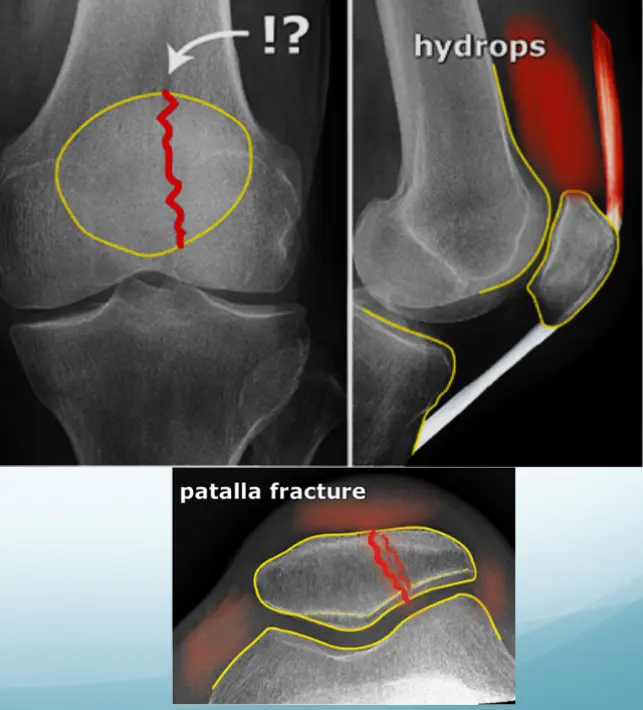

Avulsion fracture of patella

- fracture of patella

Joint Anatomy

- The annotations include:

- Joint space

- Cartilage

- Meniscus

- Joint soft tissues